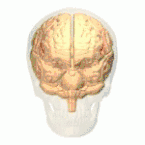

أسماء المناطق المبينة بالأرقام كما يلي:

1) القطب الجبهي ( Polus frontalis)

2) القطب القذالي ( Polus occipitalis )

3) الشق الطولاني للمخ ( Fissura longitudinalis cerebri)

4) التلفيف الجبهي العلوي ( Gyrus frontalis superior)

5) التلفيف الجبهي الوسطي ( Gyrus frontalis medius)

6) التلفيف الجبهي السفلي ( Gyrus frontalis inferior)

7) الثلم الجبهي العلوي ( Sulcus frontalis superior)

8) الثلم الجبهي السفلي ( Sulcus frontalis inferior)

9) الثلم أمام المركزي ( Sulcus praecentralis)

10) التلم المركزي ( Sulcus centralis)

11) الثلم خلف المركزي ( Sulcus postcentralis)

12) الثلم داخل الفص الجداري ( Sulcus intraparietalis)

13) الثلم الوحشي (شق سلفيوس) ( Sulcus lateralis (Fissura Sylvii))

14) التلفيف أمام المركزي ( Gyrus praecentralis)

15) التلفيف خلف المركزي ( Gyrus postcentralis)

16) الفصيص الجداري العلوي ( Lobulus parietalis superior)

17) الفصيص الجداري السفلي ( Lobulus parietalis inferior)

18) الفص القذالي ( Lobus occipitalis)

19) التلفيف الصدغي العلوي ( Gyrus temporalis superior)

20) التلفيف فوق الهامشي (؟) ( Gyrus supramarginalis)

الفص الجبهي (Frontal lobe)

الفص الصدغي (Temporal lobe)

الفص الجداري (Parietal lobe)

الفص القذالي (Occipital lobe)

الفص الحوفي (Limbic lobe)

الجَزيرَة (Insula)